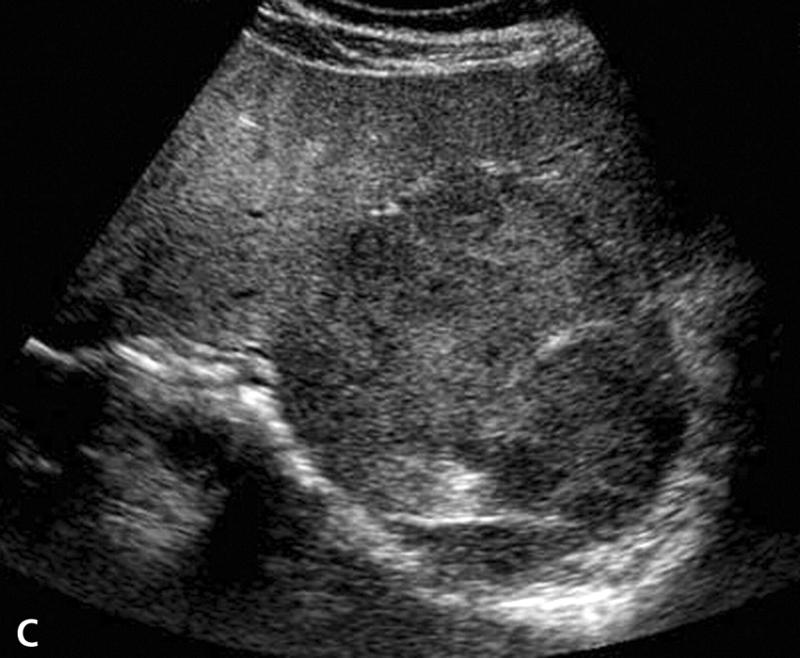

Explain the procedure of a liver exam.

Begin doing a full sweep through the liver. Starting sagittal,

slightly to the left of midline. Change to a transverse view and sweep

up and down the left lobe from a subcostal approach. Look in

transverse through the right lobe subcostally or

intercostally.

Explain the Sagittal plane for the liver exam.

The transducer may be swept under the intercostal margin to image the liver parenchyma from the anterior abdominal wall to the diaphragm.

Explain the Transverse plane for the liver exam.

The transducer should be angled in a steep cephalic direction to be as parallel to the diaphragm as possible. The transverse plan allows images of liver parenchyma, vascularity and ductal structures.